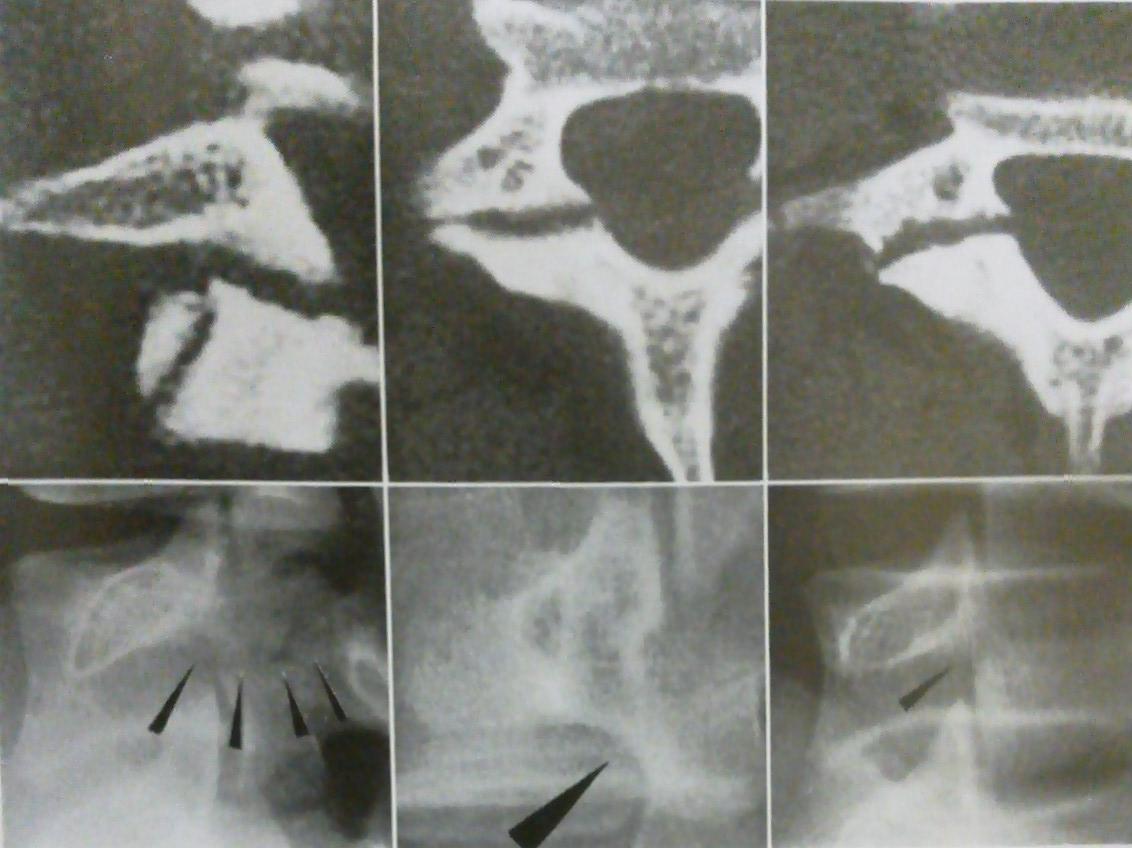

腰椎分離症・疲労骨折①

背骨と背骨を繋げている椎間関節が疲労骨折によって折れて元に戻らないままになったものを分離症と言います。

折れて椎骨(背骨)が前方へずれてしまったものをすべり症と言います。

運動部に所属している中高生に多くみられ特に野球のバットスイングのように腰を捻る動作や、バレーのサーブやスパイクを打つ時のように腰を大きく後ろへ反らすことの多い種目の選手が多いとされています。